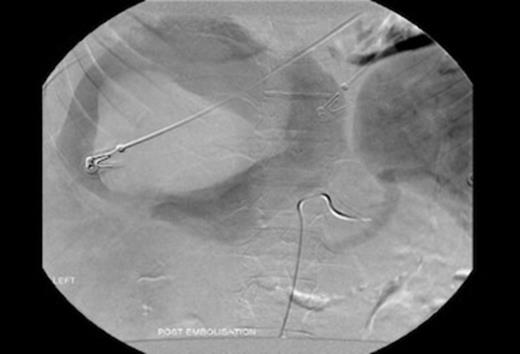

Repeat CT scan and angiography (Figures 1&2) revealed a 17cm mass occupying the right lobe of the liver with evidence of intrahepatic arterial and portal venous contrast extravasation. There was disruption of the normal right portal venous anatomy with the left portal vein being visible but displaced. Two arterial bleeding points were embolized. The underlying nature of the mass was unknown.

Indirect portography demonstrating a disruption of the intra hepatic right portal vein with extravasation of contrast into a hepatic mass.